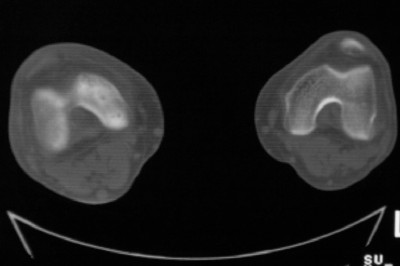

标题: CT8024:会诊!!!男 60 岁 双漆关节疼痛半年,进行性加重 [打印本页]

患者男 60 岁 双漆关节疼痛半年,进行性加重.

右股骨内髁关节面下多个不规则小囊变,边缘有明显硬化边,.......考虑: 1.关节面下骨囊变.  2.类风湿关节炎?   3.血友病?

右侧髁间隆突变尖,软骨下假囊肿形成,结合病人年龄较大,首先考虑退行性骨关节病。关节周围软组织未见明显异常,病人单单一双膝关节出现症状,不太支持类风湿性关节炎,可结合化验室检查。